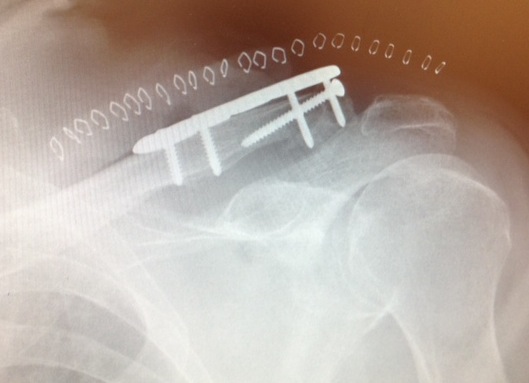

Dorsal locking plate +/- CC ligament reconstruction

Dorsal locking plate +/- CCL reconstruction

Disadvantage

Lateral screws under significant tension and subsequently higher rate of screw/plate pull-out

Indication

Sufficient lateral bone to obtain fixation

Consider having hook plate available / supplement with coraco-clavicular fixation

Dorsal locking plate with cerclage fibretape

- precontoured distal locking plate in 35 patients

- all united at mean of 4 months

- excellent outcomes scores